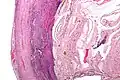

Pathology

Even for clinically certain appendicitis, routine histopathology examination of appendectomy specimens is of value for identifying unsuspected pathologies requiring further postoperative management.[75] No sign of appendicitis in specimens, negative appendectomy, varies but has been estimated to occur in 13% of specimens.[76] Notably, appendix cancer is found incidentally in about 1% of appendectomy specimens.[77][78]

Pathology diagnosis of appendicitis can be made by detecting a neutrophilic infiltrate of the muscularis propria.

Periappendicitis (inflammation of tissues around the appendix) is often found in conjunction with other abdominal pathology.[79]

Micrograph of appendicitis and periappendicitis. H&E stain

Micrograph of appendicitis showing neutrophils in the muscularis propria. H&E stain

Acute suppurative appendicitis with perforation (at right). H&E stain